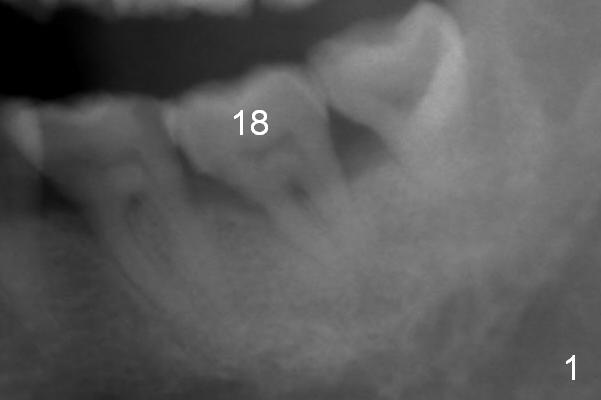

A 59-year-old man has history of chronic periodontitis (Fig.1 (taken in 2005), 2 (2014), 3 (2016)) involving the tooth #18. The bone loss may be complicated by bruxism. Large crown vs. narrow roots contributes to severe bone loss. An implant should be as long as possible and placed as coronally as possible to tackle crown/implant ratio issue. To prevent peri-implantitis, the implant may have to be placed deep. It appears that the bone height is more favorable mesially than distally (Fig.3). After extraction of the supraerupted and loose tooth (Fig.4; no Antibiotic), explore the socket to determine the favorite osteotomy site, most likely the mesial socket, lingually.